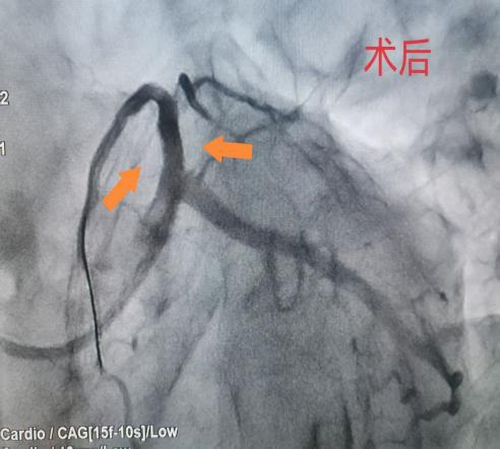

据悉,该患者因粗大前降支近段闭塞,遭受严重胸痛折磨。在接受急诊手术过程中,情况急转直下,患者突然意识丧失,心电监测显示室颤——这是一种极其危险的心律失常,如不及时处理,患者生命将在短时间内消逝。面对这一危急情况,心血管病科团队迅速反应,立即启动电除颤抢救。医护人员争分夺秒,精准操作,与死神展开了一场惊心动魄的较量。紧接着,团队成员凭借丰富的临床经验和高超的介入技术,快速完成导丝通过及支架植入,成功实现血管再通。手术的每一个环节都紧密衔接,每一个操作都精准无误,为患者的生命赢得了宝贵的时间。术后,患者逐渐苏醒,他心有余悸地感慨:“仿佛经历了一次生死轮回。”目前,患者康复状况良好,为表达对心血管病科团队的感激之情,患者特意送来一面锦旗。